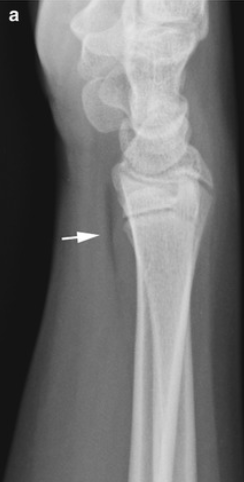

Galeazzi fractures

• Fracture of distal radius with disruption of the distal radial-ulnar joint.

• Type 1 = Dorsal displacement of the radius

• Type 2 = Volar displacement of the radius

• Notable complications: entrapment of extensor carpi ulnaris tendon or extensor digiti minimi tendon

Case courtesy of Alexandra Stanislavsky, Radiopaedia.org, rID: 10961 (Galeazzi case)